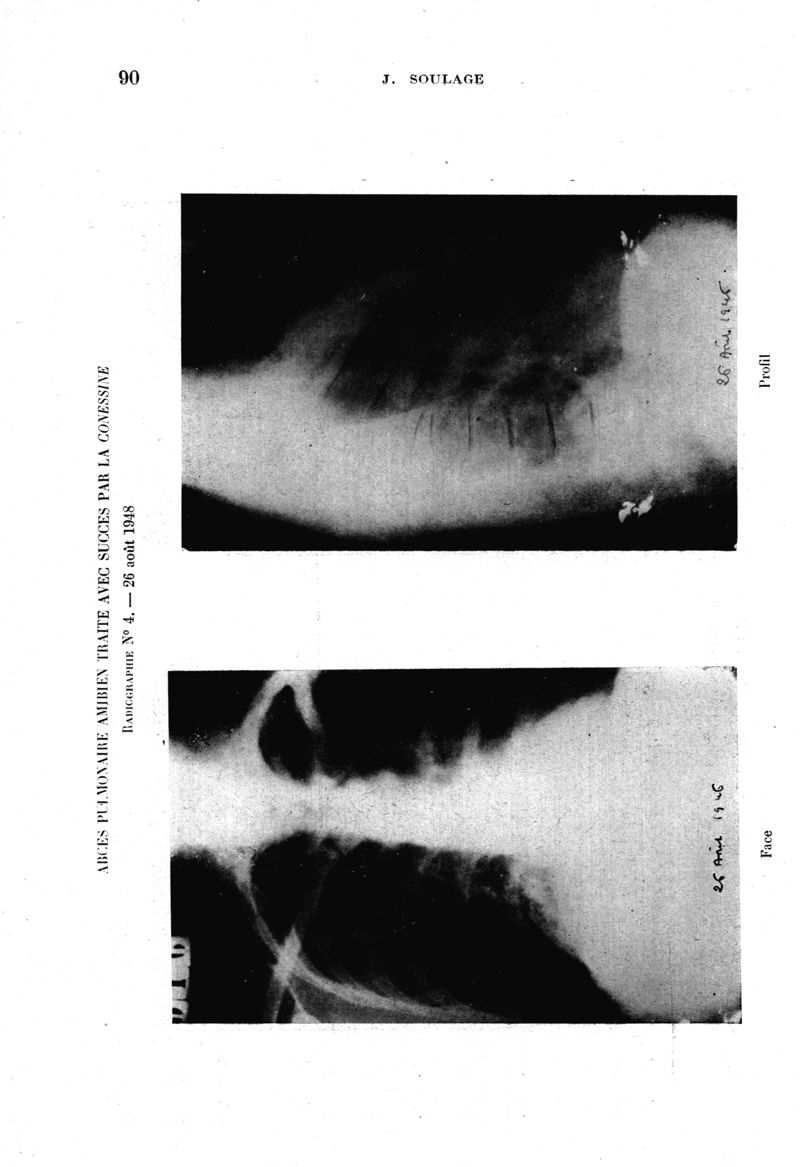

Médecine tropicale : Revue du corps de santé colonial

. - Marseille : Ecole d'application du service de santé des troupes coloniales, 1949.